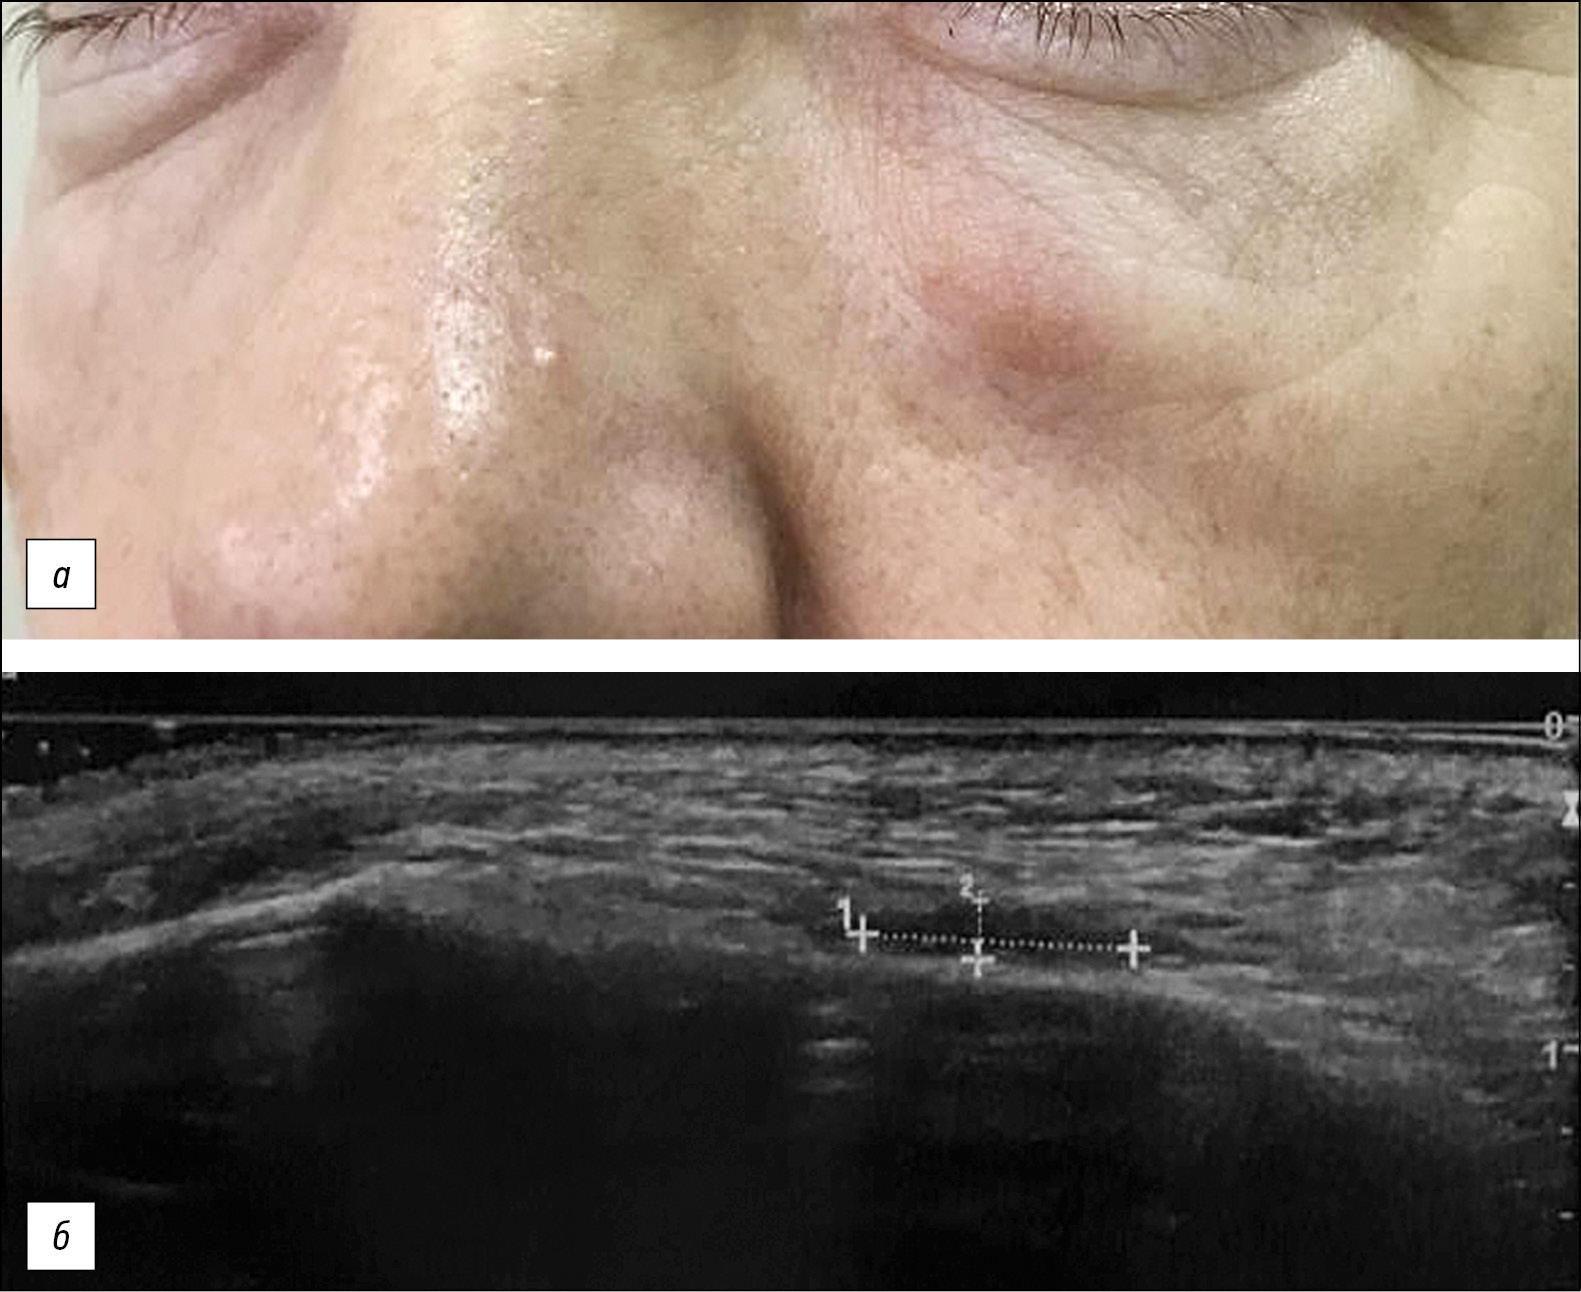

Пациентка В., 53 года. Обратилась в отделение дерматологии и косметологии АО «Институт пластической хирургии и косметологии» (Москва) с жалобами на отёк, уплотнение, покраснение, боль в области обеих носослёзных борозд (преимущественно слева) после введения филлера ГК (рис. 1, а).

Рис. 1. Пациентка В., 53 года, диагноз: L08.9 Местная инфекция кожи и подкожной клетчатки неуточнённая; T81.9 Осложнение процедуры неуточнённое. Отёк и эритема в области носослёзной борозды слева: а ― на момент обращения в клинику б ― ультразвуковое исследование кожи и мягких тканей в области левой носослёзной борозды. / Fig. 1. Patient B., 53 years old, diagnosis: L08.9 Local infection of the skin and subcutaneous tissue, unspecified; T81.9 Complication of procedure, unspecified Edema and erythema in the area of the nasolacrimal groove on the left: а ― at the time of going to the clinic; б ― ultrasound examination of the skin and soft tissues in the area of the left nasolacrimal groove.

Объективно: на момент осмотра наблюдается безболезненный локализованный слабовыраженный отёк в проекции носослёзной борозды слева, где пальпаторно определяется участок уплотнения продолговатой формы, не спаянный с окружающими тканями, без флюктуации, размером 1×1,5 см. На кожных покровах в области воспаления отмечается эритема умеренной интенсивности. Область левой носослёзной борозды без изменений.

По данным ультразвукового исследования (УЗИ) в проекции носослёзных борозд наднадкостнично определяются анэхогенные включения препарата, характерные для препаратов на основе ГК по УЗ-картине, с признаками перифокального фиброза: справа 5,8×1,4 мм, слева 8,2×1,8 мм. УЗ-признаков отёчно-инфильтративных изменений тканей не выявлено (рис. 1, б).